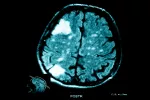

Los cerebros de los niños y adolescentes con TDAH (trastorno de hiperactividad y déficit de atención) son más lentos a la hora de formar las conexiones internas y entre las redes cerebrales, que los de otros menores de la misma edad que no presentan esta patología, según se ha observado en una investigación publicada en Proceedings of the National Academy of Sciences (PNAS).

Los investigadores, del Departamento de Psiquiatría de la Facultad de Medicina de la Universidad de Michigan (EE.UU.), examinaron imágenes cerebrales obtenidas mediante resonancia magnética, para observar cómo distintas redes cerebrales, con diversas funciones, se comunican interiormente y entre ellas, y comprobaron que existían retrasos en el desarrollo de ciertas conexiones, especialmente en dos zonas específicas del cerebro, donde otras investigaciones sobre la estructura física de los cerebros de pacientes con TDAH ya habían encontrado alteraciones.